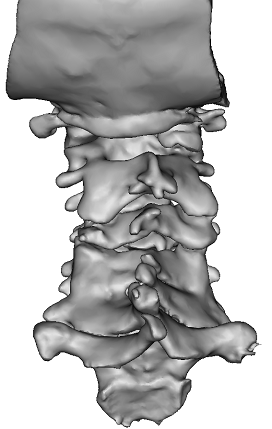

患者安某,因外伤致后颈脊髓损伴高位截瘫收入我院脊柱创伤外科,经放射检查和三维重建发现该患者颈椎明显畸形,常规的颈椎后路长节段减压内固定手术中的后路置入椎弓根螺钉非常困难,极易突破椎弓根,伤及附近血管和神经。

术前颈椎三维重建显示椎体畸形